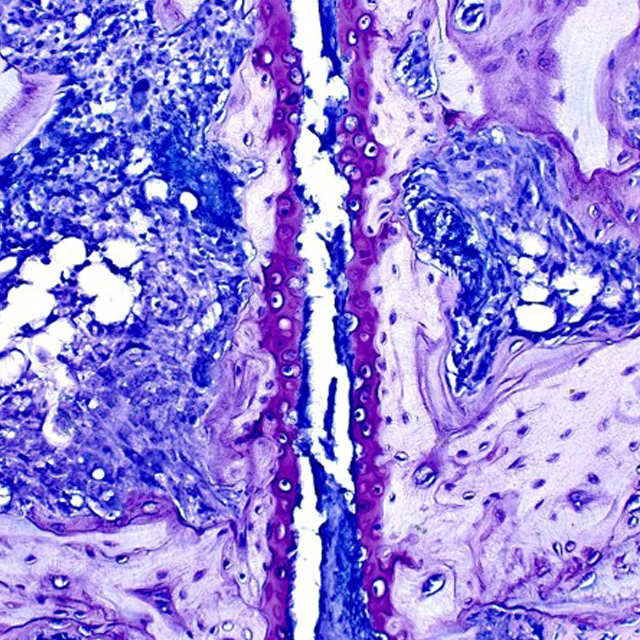

Collagen-Induced Arthritis [CIA] Model

류마티스 관절염의 글로벌 Gold-Standard 모델

마우스와 랫드 CIA 모델의 품질은 시험 결과의 정확성을 결정짓는 가장 중요한 요소입니다. 류마티스 관절염과 가장 유사한 발병기전을 보이는 검증된 CIA 모델을 이용하여 고품질 유효성 평가를 서비스합니다.